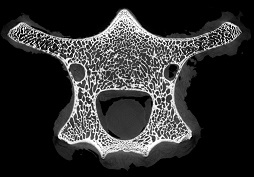

脊椎骨里的“笑臉表情包”

micro CT不僅能夠獲得整體骨量的變化,還能獲得骨骼內部骨小梁骨微結構的定量指標,進而將骨小梁微結構指標、皮質骨指標及骨量結合起來,綜合評價骨強度和骨量在骨質疏松癥發生和發展中的作用。